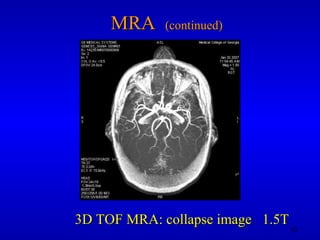

MRA  (continued) 3D TOF MRA: collapse image  1.5T

MRA (continued)3D TOF MRA: collapse image 1.5T